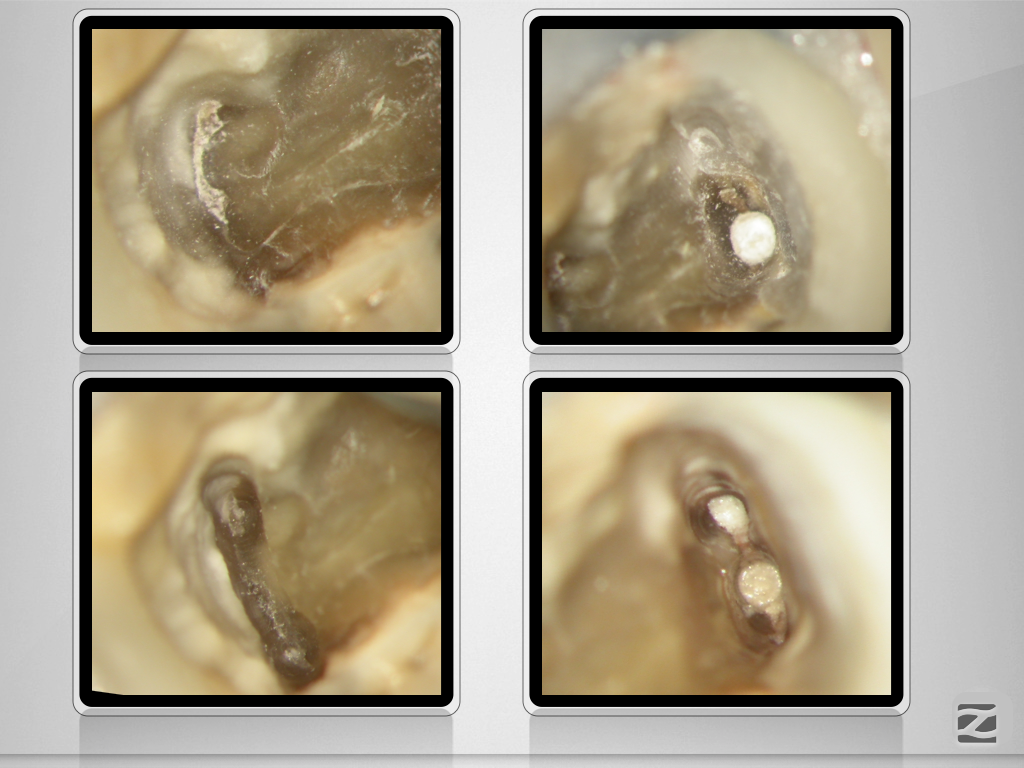

46D.010

Tiefe Gabelung mit 90 Grad nach distal